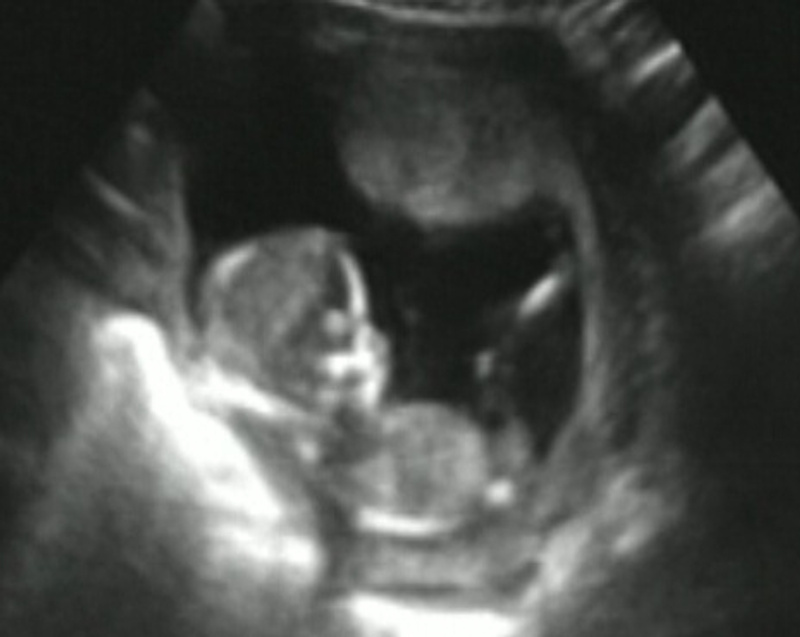

• вот наше чудо..лежит себе в гамаке. 75 грамм весит...

Никогда не говори никогда.

• Ой какая прелесть и руки за головой?

Нет фразы "я не могу", есть фраза "я ленивая скотина"... (с)

• ага.и ножки вытянула... весь сеанс так и продрыхла, в самом конце только попкой повернулась:улыб:

• В ответ на: вот наше чудо..лежит себе в гамаке. 75 грамм весит...

Ути.....:улыб: :wub1.gif:

Это вы в 12 неделек такие были?

• ага. 12 недель.. кажется такой маленький срок.. а уже совсем человечек!!!